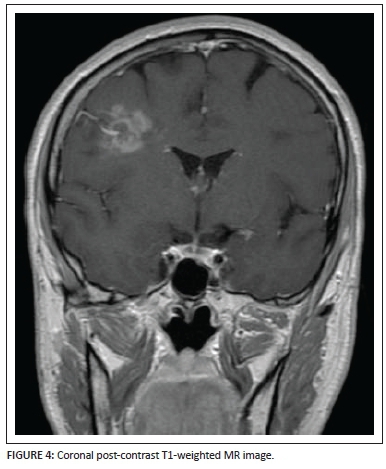

Coronal (Figure 4) and axial (Figure 5) post-gadolinium T1-weighted sequences demonstrate the patchy enhancement of the major portion of the lesion except for the focal areas of necrosis centrally within the lesion bed. The enhancing vessel is well demonstrated, extending from the pial surface through the centre of the lesion. Subtle brush-like vascular enhancement is also seen in the contralateral centrum semiovale white matter.